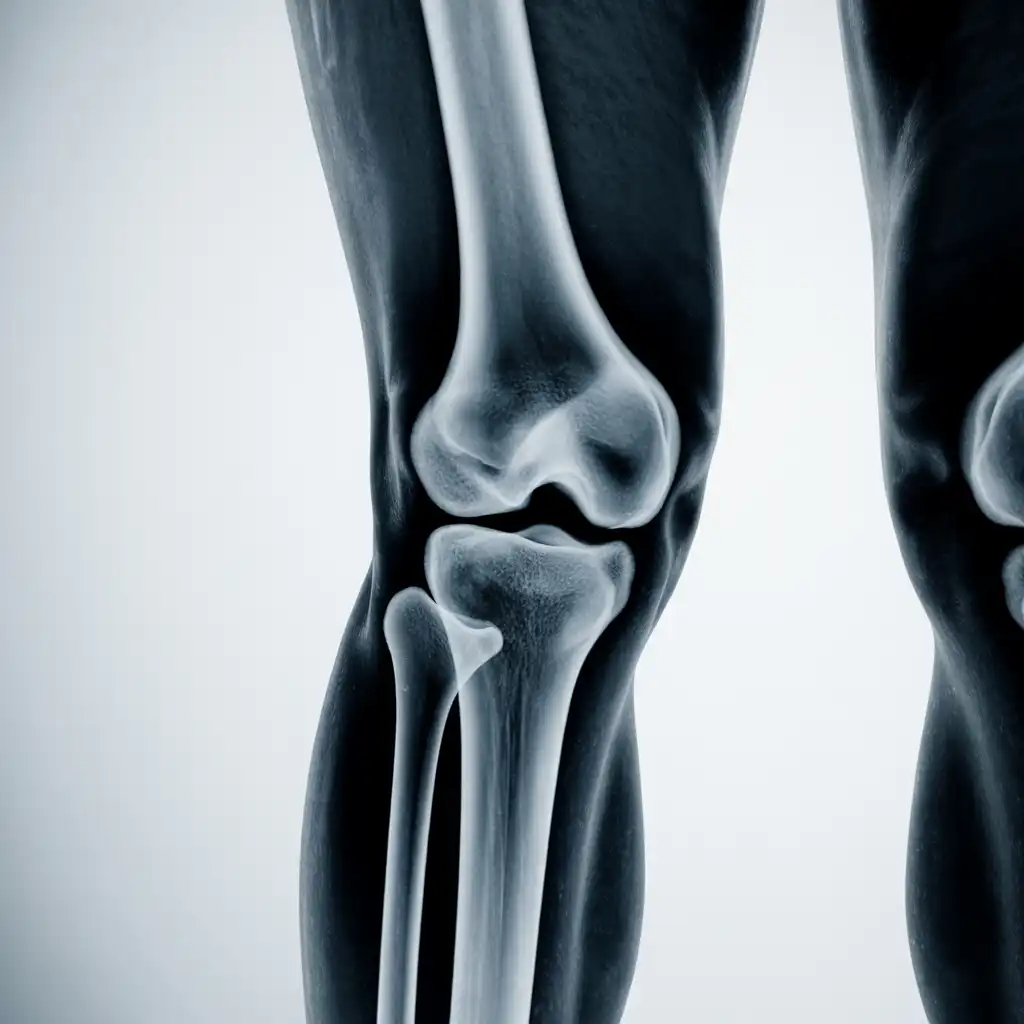

Una lastra a domicilio è una radiografia eseguita direttamente a casa del paziente, grazie all’intervento di un tecnico sanitario qualificato dotato di apparecchiatura digitale portatile.

L’esame viene effettuato sul posto, senza necessità di spostare la persona dal letto o dalla poltrona, e garantisce una qualità diagnostica paragonabile a quella di un reparto ospedaliero.

Nel corso degli anni abbiamo effettuato migliaia di radiografie a domicilio in abitazioni private, RSA, centri di assistenza e strutture per anziani, utilizzando apparecchi digitali portatili certificati che garantiscono immagini precise e tempi di esecuzione rapidi.